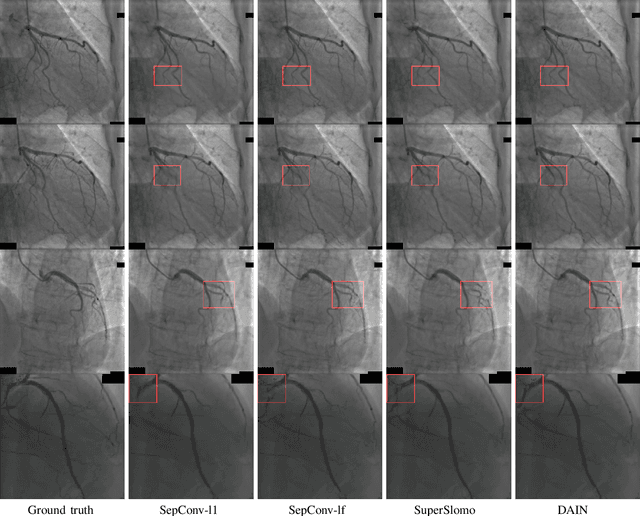

Cardiac coronary angiography is a major technology to assist doctors during cardiac interventional surgeries. Under the exposure of X-ray radiation, doctors inject contrast agents through catheters to determine the position and status of coronary vessels in real time. To get a coronary angiography video with a high frame rate, the doctor needs to increase the exposure frequency and intensity of the X-ray. This will inevitably increase the X-ray harm to both patients and surgeons. In this work, we innovatively utilize a deep-learning based video interpolation algorithm to interpolate coronary angiography videos. Moreover, we establish a new coronary angiography image dataset ,which contains 95,039 triplets images to retrain the video interpolation network model. Using the retrained network we synthesize high frame rate coronary angiography video from the low frame rate coronary angiography video. The average peak signal to noise ratio(PSNR) of those synthesized video frames reaches 34dB. Extensive experiment results demonstrate the feasibility of using the video frame interpolation algorithm to synthesize continuous and clear high frame rate coronary angiography video. With the help of this technology, doctors can significantly reduce exposure frequency and intensity of the X-ray during coronary angiography.